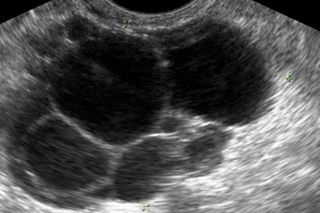

Rebecca Campbell: We are doing work in a pre-clinical model of PCOS, using rodent models that allow us to take advantage of different neuroscience tools so we can look at specific circuits in the brain. This model is reflective of a lean PCOS phenotype. PCOS tends to either exhibit phenotype that’s dissociated with metabolic syndrome so obesity, insulin those types of things. That’s currently thought to be about half of the PCOS women that are diagnosed. The other half of women that are being diagnosed with PCOS don’t tend to have a metabolic phenotype. So we refer to them as the lean PCOS phenotype. But interestingly this group appears to have more severe infertility issues. Our model exhibits a lot of the same characteristics. It has high androgen levels, so high testosterone. The ovaries look like a polycystic ovary and they are essentially infertile. So what we’ve been interested in looking at is how the brain might be involved in regulating the things that are happening in the ovary.